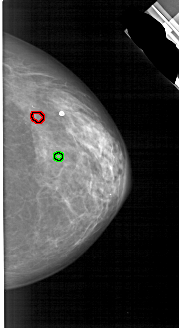

A_1791_1.LEFT_CC

LEFT_CC LINES 5041 PIXELS_PER_LINE 2626 BITS_PER_PIXEL 12 RESOLUTION 43.5 NON_OVERLAY

FILE: A_1791_1.RIGHT_CC.OVERLAY

TOTAL_ABNORMALITIES 1

ABNORMALITY 1

LESION_TYPE CALCIFICATION TYPE PLEOMORPHIC DISTRIBUTION CLUSTERED

ASSESSMENT 4

SUBTLETY 2

PATHOLOGY BENIGN

TOTAL_OUTLINES 1

BOUNDARY

ABNORMALITY 2